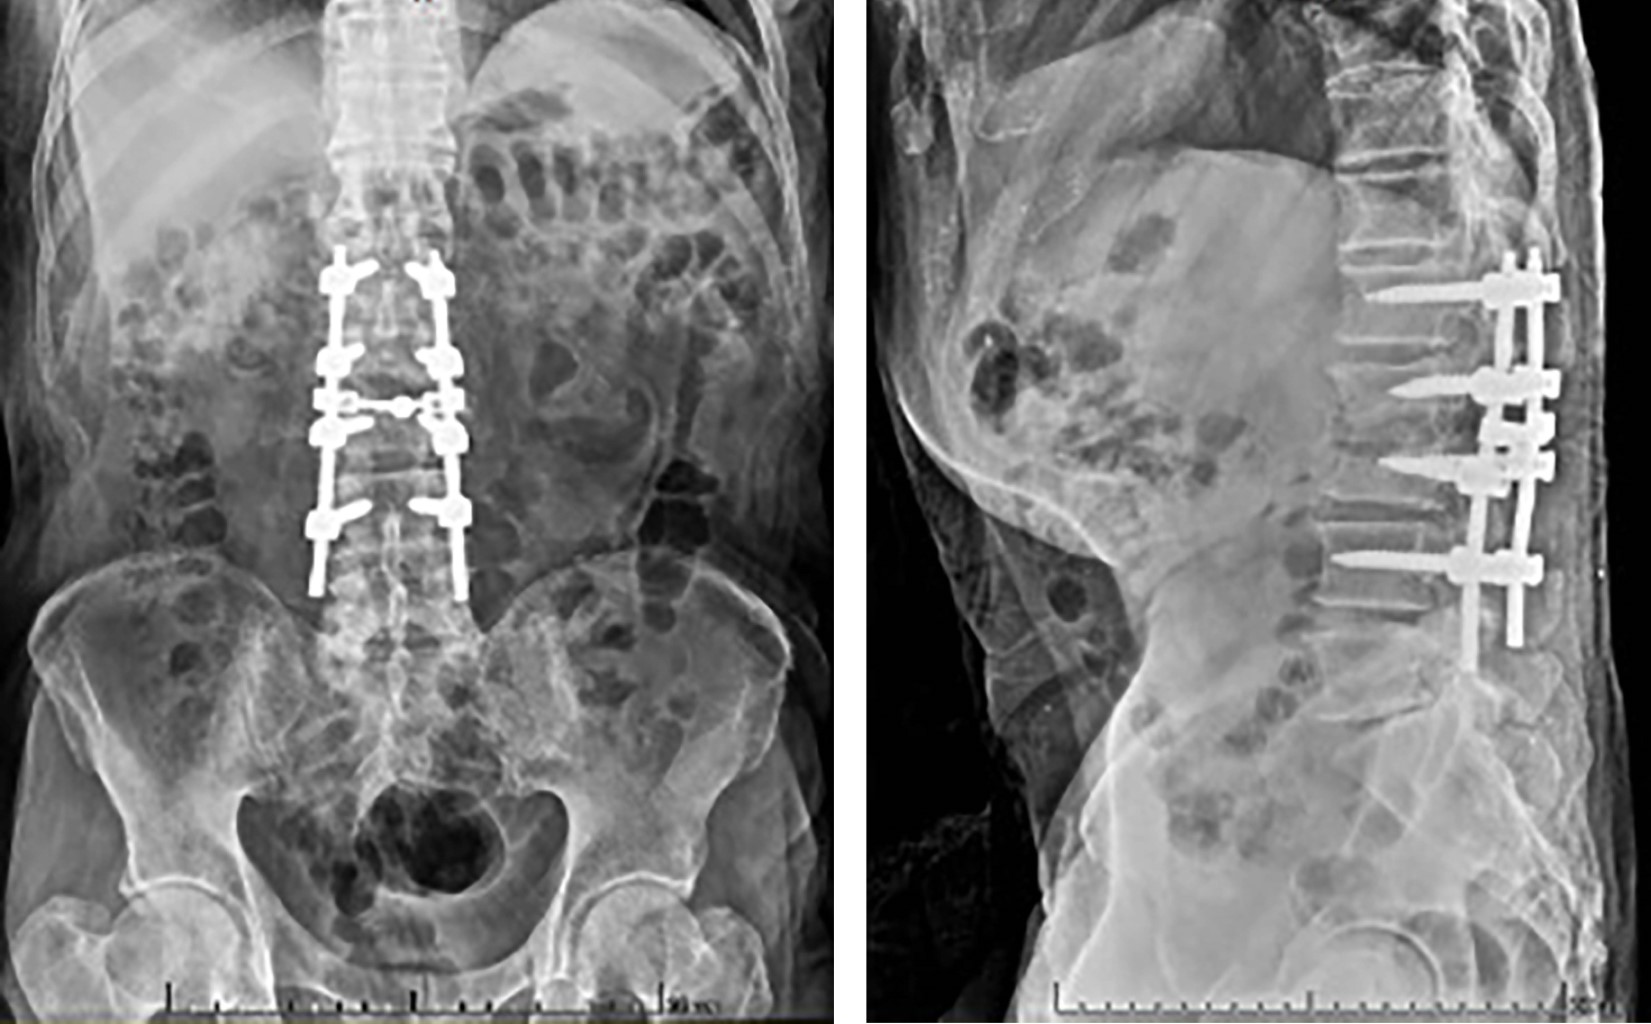

Se obtuvo un total de 51 pacientes diagnosticados con síndrome de destrucción vertebral (Figura 1 y 2). Se observó una incidencia mayor para el género masculino (n = 34) y que para el femenino (n = 17). La edad promedio fue 64.66 años (rango 25 a 85 años). Los cuerpos vertebrales afectados con mayor frecuencia fueron L4 con 18 casos, L2 con siete, L5 con siete y L3 con 11. En nuestra población, la primera causa del síndrome de destrucción vertebral fue de origen neoplásico con 34 casos confirmados mediante reporte histopatológico, seguido por los de origen infeccioso con nueve casos y, por último, los de origen metabólico con ocho casos.